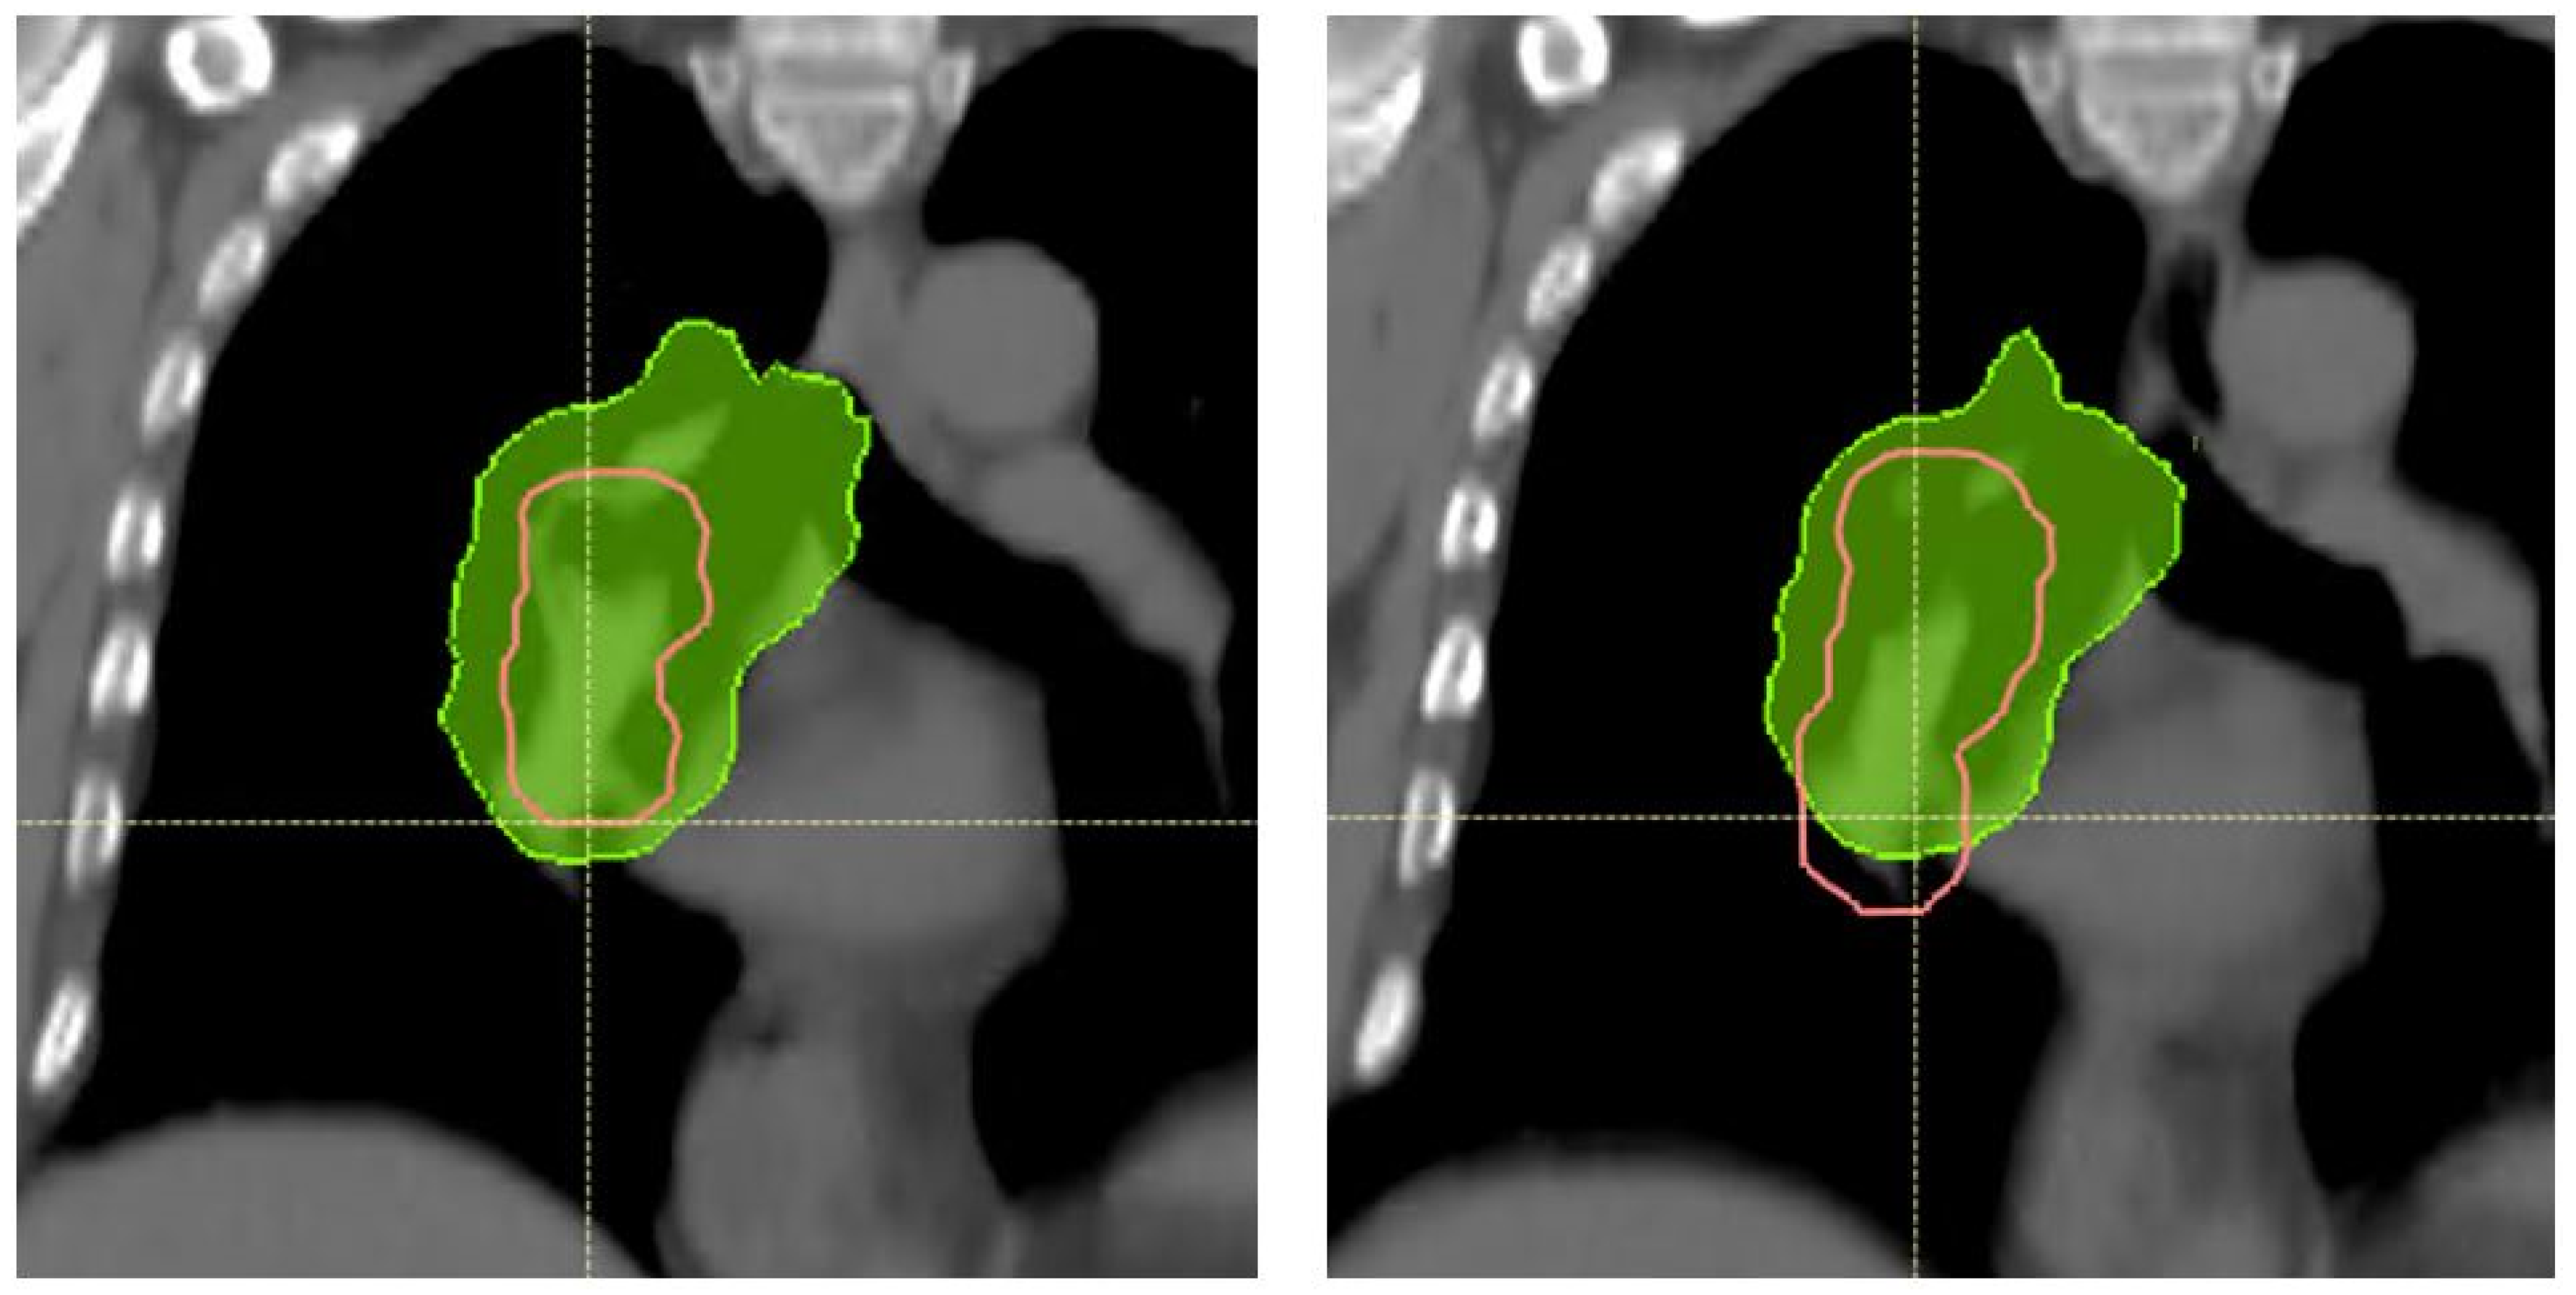

- Ribeiro, C.O.; Visser, S.; Korevaar, E.W.; Sijtsema, N.M.; Anakotta, R.M.; Dieters, M.; Both, S.; Langendijk, J.A.; Wijsman, R.; Muijs, C.T.; et al. Towards the Clinical Implementation of Intensity-Modulated Proton Therapy for Thoracic Indications with Moderate Motion: Robust Optimised Plan Evaluation by Means of Patient and Machine Specific Information. Radiother. Oncol. 2021, 157, 210–218. [Google Scholar] [CrossRef] [PubMed]

- Hoffmann, L.; Alber, M.; Jensen, M.F.; Holt, M.I.; Møller, D.S. Adaptation Is Mandatory for Intensity Modulated Proton Therapy of Advanced Lung Cancer to Ensure Target Coverage. Radiother. Oncol. 2017, 122, 400–405. [Google Scholar] [CrossRef]